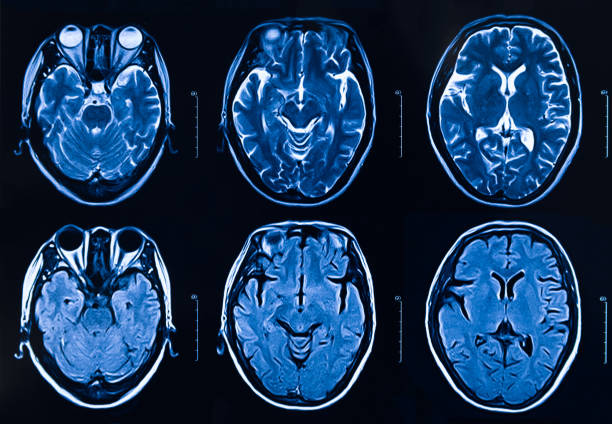

本研究纳入2018年1月1日至2020年10月31日发病168小时内发生急性ICH的患者。间充质干细胞被静脉注射给9名患者(5名女性,4名男性),平均年龄(范围)为61(36-84)岁。表1总结了人口统计学和临床特征 。出于描述目的,患者按照入组顺序获得编号,并连续分配到三组中的一组,每组三人。根据模型 2 分割,ICH体积范围为0.1至54.9mL(平均ICH体积为23.5mL)。5例ICH累及局部脑叶,其余则位于基底节或外囊深处。在三名患者中,ICH位于丘脑(图1),在一名患者中,血肿位于多个脑结构(即尾状核、壳核和苍白球)。平均而言,MSC在ICH后3天进行注射。